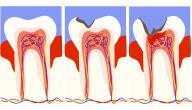

يعتبر تسوّس الأسنان من المشاكل الشائعة بين الناس، لا سيّما مع ازدياد تناول السكاكر والحلويات بمختلف أنواعها، فإذا لم يتّبع كل فرد سبل العناية الصحيحة بالأسنان فإنّها ستكون عرضة لحدوث التسوّس، حيث تتخرّب بنية الأسنان المتسوّسة، فتصاب بالتعفّن الذي يمكن أن يتطور تدريجياً إلى ثقوب صغيرة أو كبيرة بصورة تدريجيّة، وقد يتطوّر ضعف السنّ في حال لم تتمّ معالجته فور إصابته، ويكون علاجه في الغالب عن طريق إزالة الجزء التالف، واستبداله بحشوة صناعيّة، وممّا تجدر الإشارة إليه أنّها تشكّل حلّاً مثالياً في حالة الأسنان المتهتّكة أو المتشقّقة أيضاً.